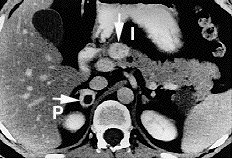

ورم خلايا الجزيرة أو ورم عصبي-صماوي بنكرياسي أو ورم صماوي بنكرياسي[1] هو نوع سرطاني غير شائع يصيب الغدد الصماء في البنكرياس.

تشكل تقريبًا 1.3% من سرطان البنكرياس.[2]